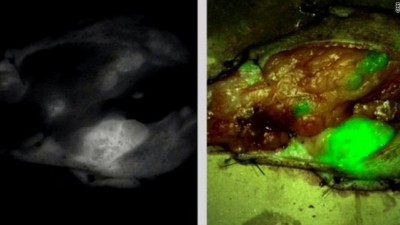

الصورة التي على اليسار مأخوذة من فحص أشعة والثانية تمثل لورم جرى تلوينه بسم العقرب

إنه أصعب أمر، حيث لا بد أن يترك تقدير ذلك إما لجراح ماهر أو الحظّ. ففي الوقت الذي تلمع فيه الخلايا السرطانية أثناء التصوير بالأشعة، إلا أنها تبدو مماثلة للخلايا غير المصابة أثناء الجراحة.

مكنت تلك التجربة أولسن وفريقه من التوصل إلى بروتين يفرزه سم العقرب ونجح في تحويله إلى "ملون للورم." فقد نجح ذلك البروتين في تحييد ورم كامل في فأر و"جمعه" إلى بعضه البعض في غضون ساعة بحيث كان من السهل على العين المجردة التعرف إلى ما ينبغي إزالته وما ينبغي عدم لمسه، فهو أكثر فعالية بما لا يقل عن 500 مرة من فحص الأشعة.